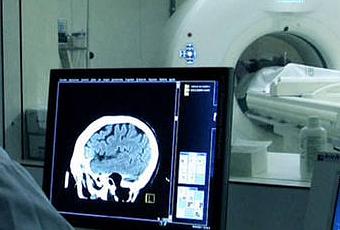

Recientemente, y recientemente estamos hablando en los últimos 10 años, se han desarrollado unos biomarcadores que, o a través del análisis del líquido cefalorraquídeo, o a través de una tecnología más sofisticada que es la tecnología PET, que es la tomografía de emisión de positrones, permite detectar ese beta-amiloide en una persona que está viva. ¿Cómo se hace esto? Se extrae una muestra del líquido cefalorraquídeo a través de lo que se denomina una punción lumbar y se analiza los niveles de beta-amiloide que contiene ese líquido, los niveles de Tau con lo cual de una forma viva estás viendo lo que la anatomía patológica te diría si analizáramos el cerebro en ese momento.